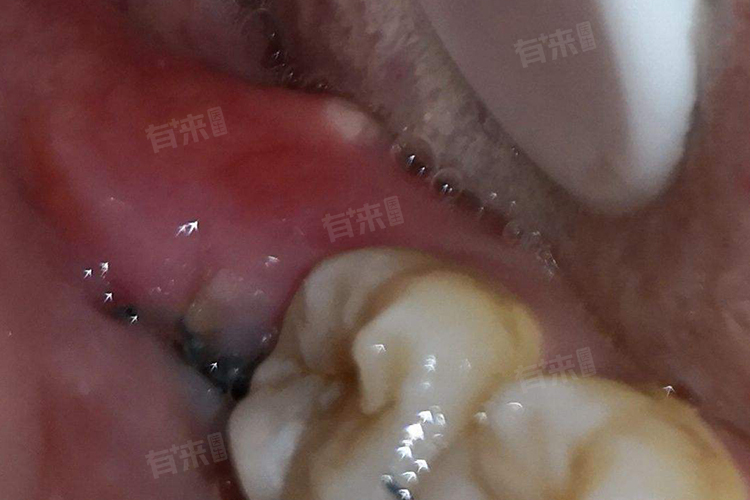

- 智齿拔除是一种常见的口腔手术,很多人会考虑在哪个季节进行更为合适。夏天由于气温较高,人们容易出汗,可能会增加伤口感染的风险,但是并不意味着夏天就完全不适合拔智齿。

但是夏天拔牙也有一些需要注意的地方,拔牙后要更加注意口腔卫生。由于夏天出汗多,口腔内的细菌容易滋生,所以要勤漱口,保持口腔清洁,可以使用医生推荐的漱口水,按照正确的方法进行漱口。并且要避免食用辛辣、刺激性食物和过热的食物,这些食物可能会刺激伤口,引起疼痛和出血。还要注意休息,避免剧烈运动和过度劳累。